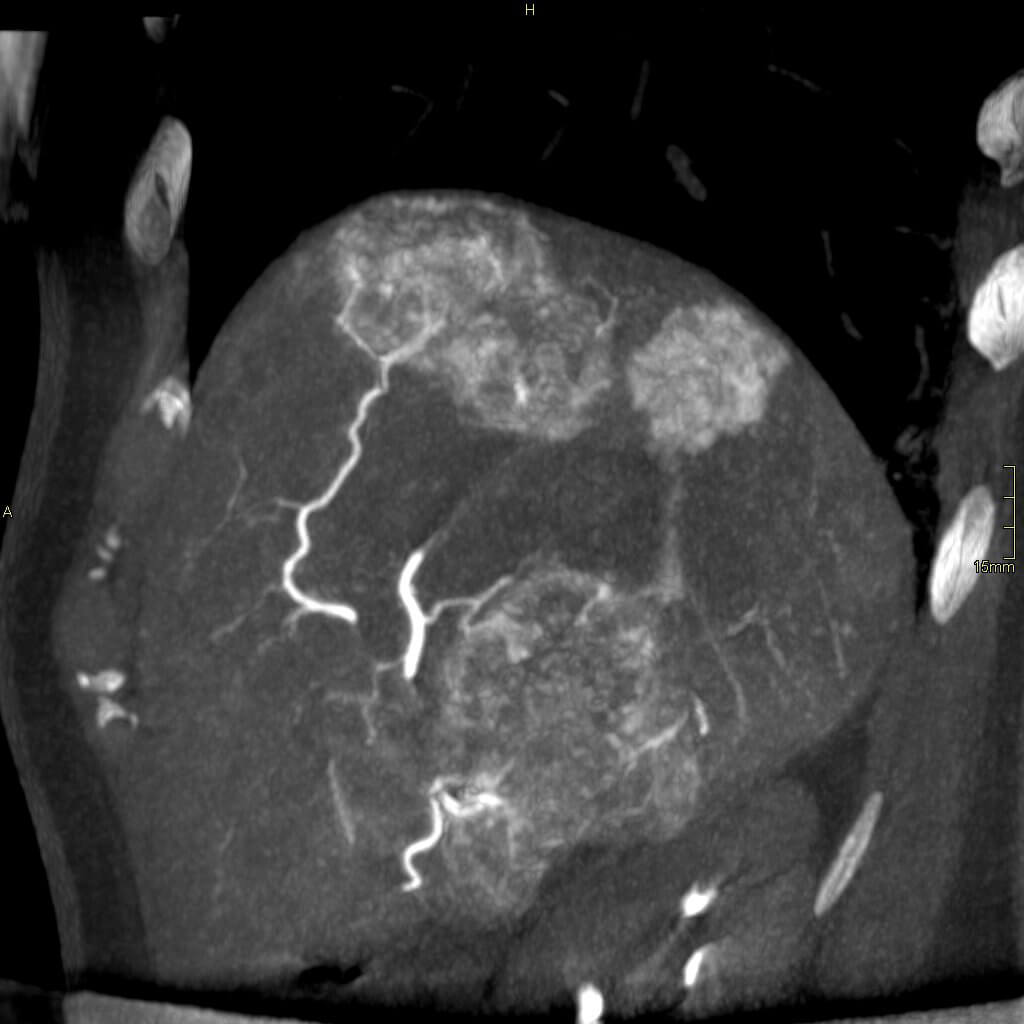

TriNAV is a handy catheter and so far has added value to our patient’s treatments. Especially Sirtectomies (Sirtex segmentectomies). Only drawback is the smaller lumen and the higher PSI required to get some of the flow rates needed for imaging. Really challenging with the Mark7 injector and its 900 PSI max limit. Lucky for us our Nemoto Press Duo injector has a 1200 PSI max limit and we can adjust contrast concentration on the fly improving our odds of getting both a well injected and properly dosed cone beam CT dataset.